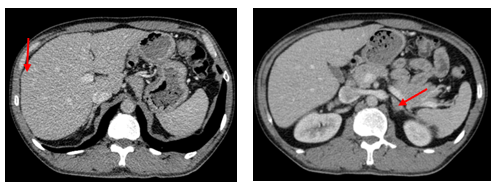

- Chụp cắt lớp vi tính lồng ngực: phim trước điều trị

Hình 1. Trên phim chụp CT lồng ngực ở cửa sổ nhu mô: thùy trên phổi trái có khối đặc tròn bờ tua gai, kích thước: 29 x20mm, kính mờ và dày kẽ xung quanh, lân cận có nốt bán đặc kích thước 29 x 17mm, ngấm thuốc không đồng nhất sau tiêm, nghi ngờ có phần xâm lấn trung thất trước. Nhu mô thùy còn lại và nhu mô phổi phải lan tỏa các nốt đặc tròn to nhỏ không đều, đường kính: 2-8mm.

Hình 2. Cửa sổ trung thất: Vài hạch trung thất cạnh khí, hạch lớn nhất kích thước 14x7mm

- Cắt lớp vi tính lồng ngực:

Sau 3 tháng điều trị đích:

- U nguyên phát và u thứ phát ở cả 2 phổi đều giảm kích thước rất nhiều, không thấy hạch trung thất.

Sau 6 tháng điều trị:

- U nguyên phát chỉ còn kích thước rất nhỏ, u thứ phát 2 bên phổi đã mất hết.